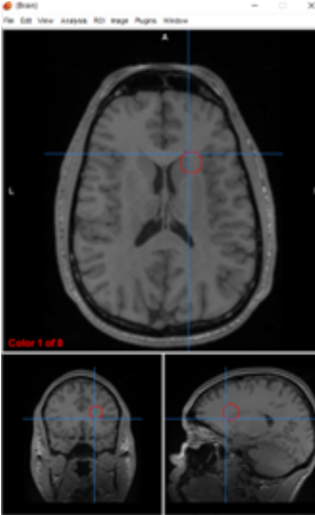

amygdalae

emotional processing, fear conditioning, and memory

amygdala

primary center for emotional processing, fear conditioning, and threat detection